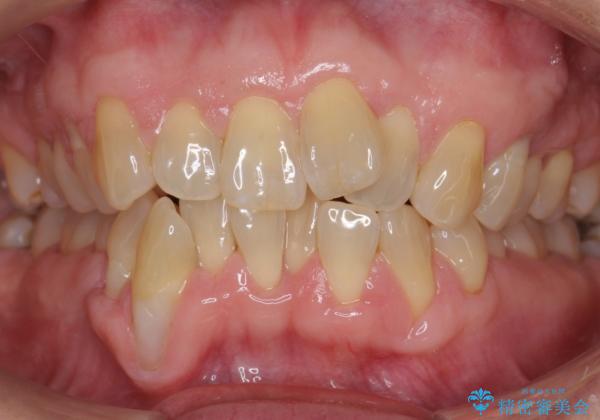

前歯のがたつき インビザラインで抜歯矯正

右下の犬歯の1本抜歯で最小限の抜歯で並べることができました。

奥歯も上下交互になるようにかみ合わせることができました。